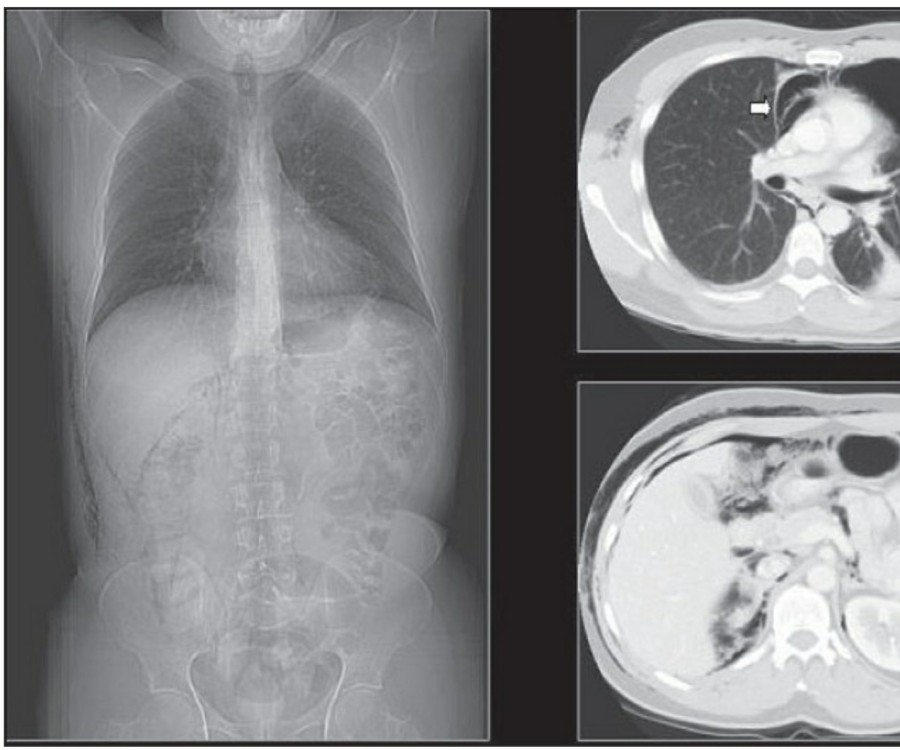

중환자에서 pneumothorax의 진단은 종종 supine radiograph에서 내릴 수 있다. Supine position에서 공기는 anteromedial 방향으로 모이게 되는데, apical air collection이 있을 경우 large pneumothorax가 있음을 시사한다. 공기는 lung과 diaphragm 사이의 subpulmonic location에 trap 되어 있을 수도 있다. 공기가 costophrenic sulcus로 anterolateral extension 될 경우, 이 costophrenic sulcus의 radiolucency를 증가시키는데, 이를 deep sulcus sign이라고 한다. Subpulmonic pneumothorax의 다른 특징으로 diaphragm의 superior surface와 IVC 윗부분이 뚜렷하게 보일 수 있다.

중환자에서 tension pneumothorax의 진단은 매우 힘들다. ARDS와 같은 lung의 병리적인 기전이 lung compliance를 감소시킴으로써 total lumg collapse를 막는다. 또한 tension pneumothorax의 특징인 mediastinal shift가 PEEP으로 인해 나타나지 않을 수 있다. Chest X ray 상에서 tension pneumothorax는 hemidiaphragm의 depression이나 heart border, SVC, IVC의 이동으로 나타날 수 있다.